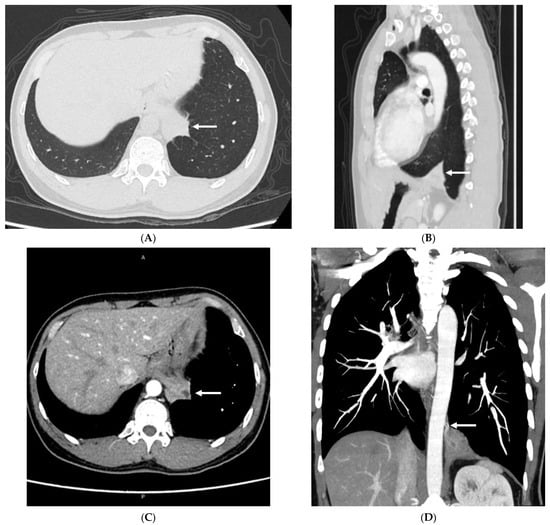

Computed Tomography Imaging Features of Pulmonary Sequestration

3. Results

3.2. Imaging Appearances of CTPA